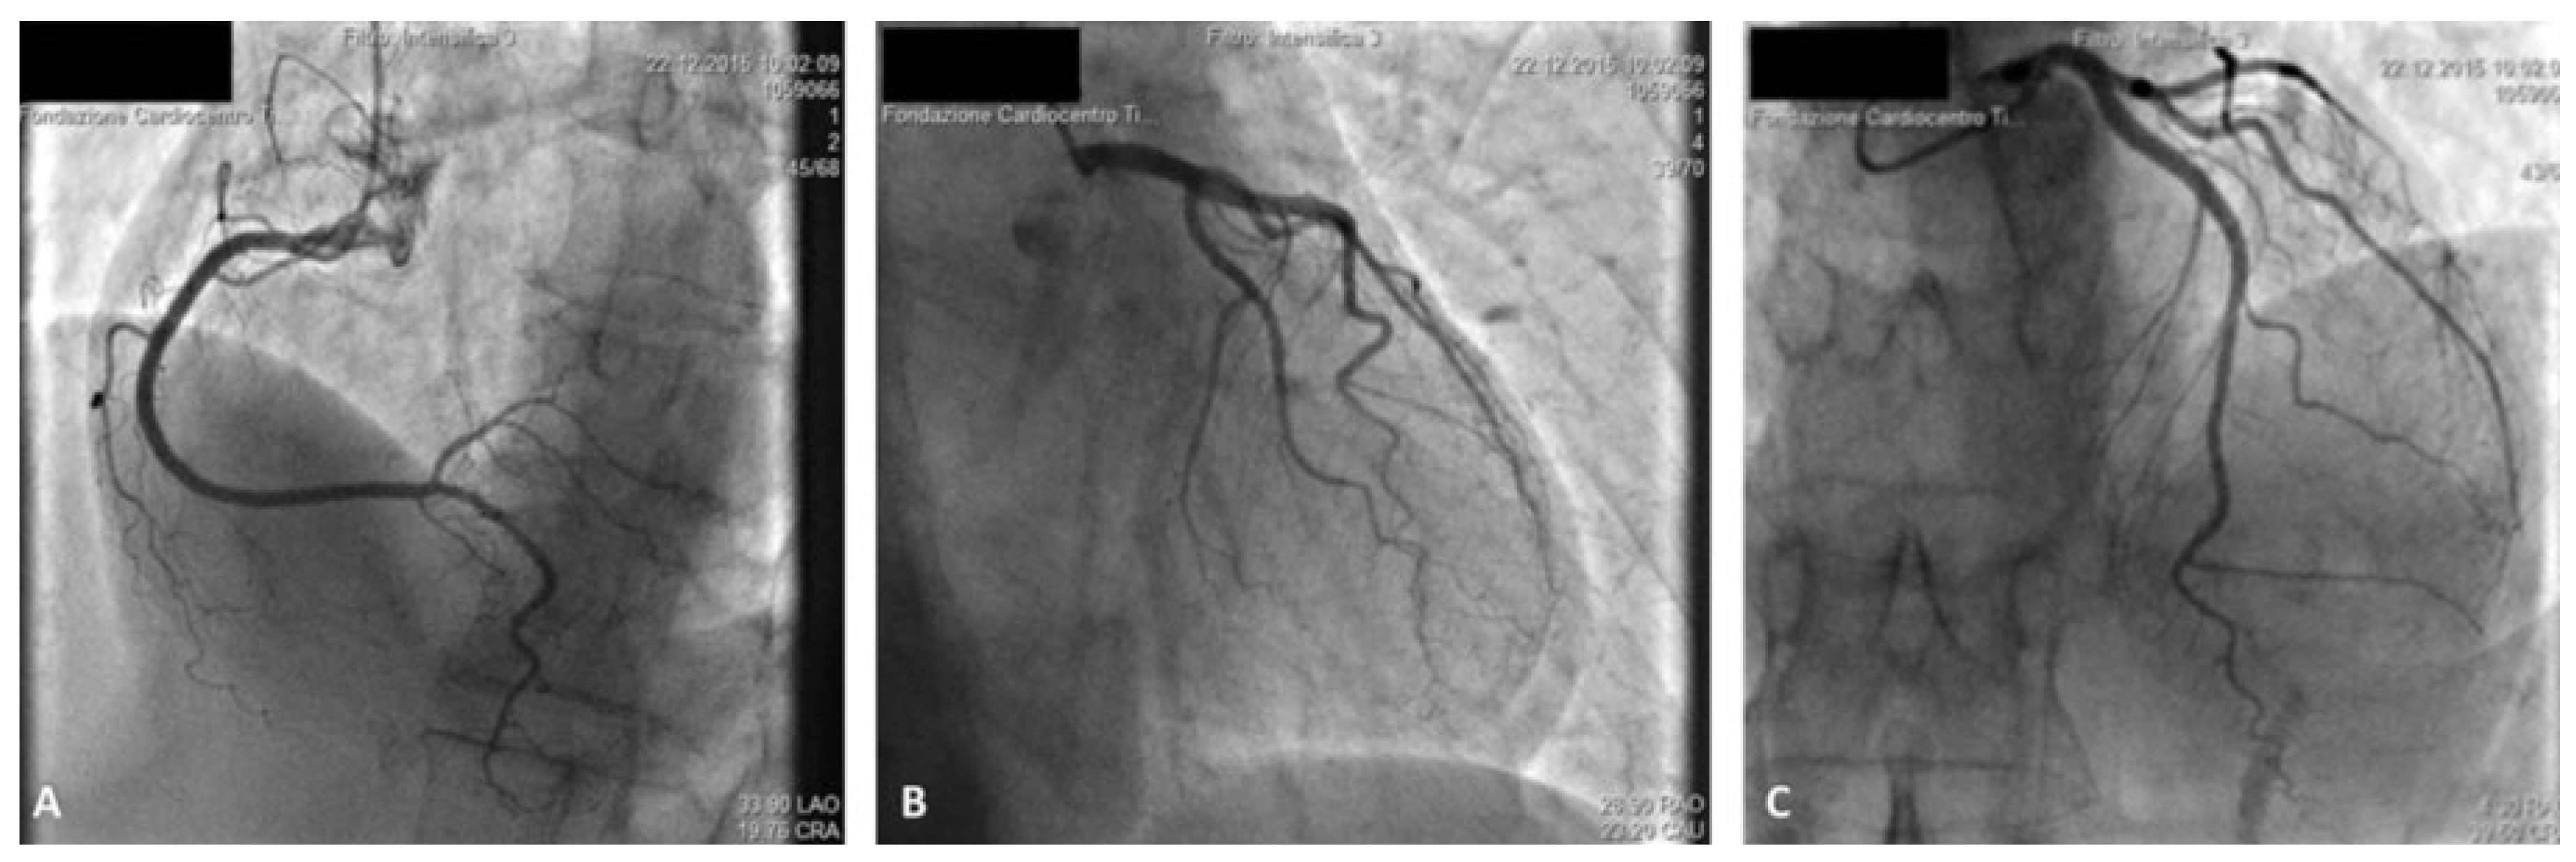

Case report